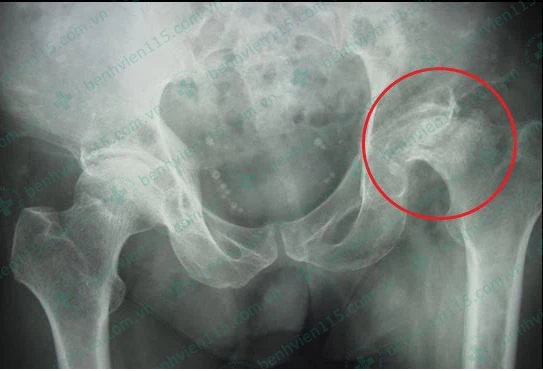

Kết quả chụp X-quang cho thấy bệnh nhân bị hoại tử chỏm xương đùi. (Ảnh do BV cung cấp)

Sau khi chẩn đoán, các bác sĩ (BS) kết luận ông T. bị hoại tử chỏm xương đùi, nguyên nhân chính dẫn đến tình trạng này là do rượu bia và thuốc lá. Bản thân ông T. cũng cho biết đã "làm bạn" với rượu bia, thuốc lá từ năm 20 tuổi.

Cũng theo BS Hoa, vùng hoại tử lúc đầu chỉ là vùng thưa xương và các ổ khuyết xương. Dần dần dẫn đến tình trạng gãy xương dưới sụn và giai đoạn cuối là gây xẹp chỏm xương đùi. Hiện tượng trên làm mất chức năng bình thường của khớp háng khiến người bệnh trở nên tàn phế.